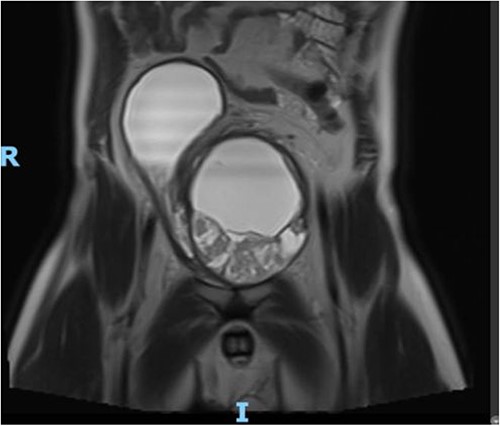

The patient presented to the ED 3 months later with urinary retention and pain; this was relieved with catheterization. A CT scan revealed that his tumor had slightly increased in size (Fig. 1). He had an AUA symptom index of 35. Due to the refractory nature of his obstructive symptoms, he was scheduled for a TURP 2 weeks later, which again revealed leiomyoma. He was kept on interval follow-up for the next 2 years. During that time his PSA was 1.13 ng/ml. Magnetic resonance imaging (MRI) pelvis 2 years later showed the mass appeared to communicate with the posterior bladder neck (Fig. 2). His baseline renal function kept worsening (Creatinine 1.4 mg/dl); at that time, the patient was counseled regarding his treatment options, and he opted for surgery which he was told may require the removal of the prostate with loss of ejaculatory and/or erectile function.

MRI Pelvis (contrast) June 2021: well-marginated complex solid, cystic, and septated pelvic mass with multiple sites of enhancement and restricted diffusion; the mass appears to communicate with the bladder neck.